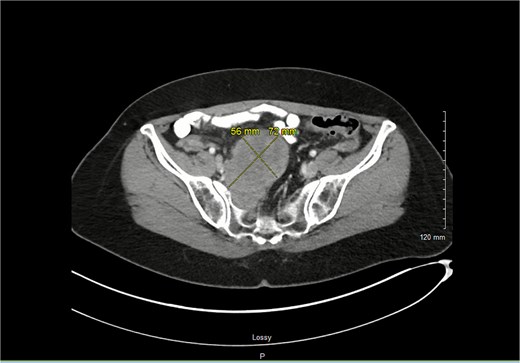

A 62-year-old female presented to the office for multiple bouts of diverticulitis. Cross-sectional imaging from her most recent bout of diverticulitis showed a peripheral nerve sheath tumor located on the right spinal column that measured 56 × 72 mm (Fig. 1), abutting the iliac vessels, which at the time was not in proximity of the sigmoid colon. The patient had known about this tumor for quite some time. She had met with a neurosurgeon, but given its benign features and her lack of symptoms, no further intervention was offered.

Axial imaging shows the schwannoma with greatest measurements of 7.2 × 5.6 cm.